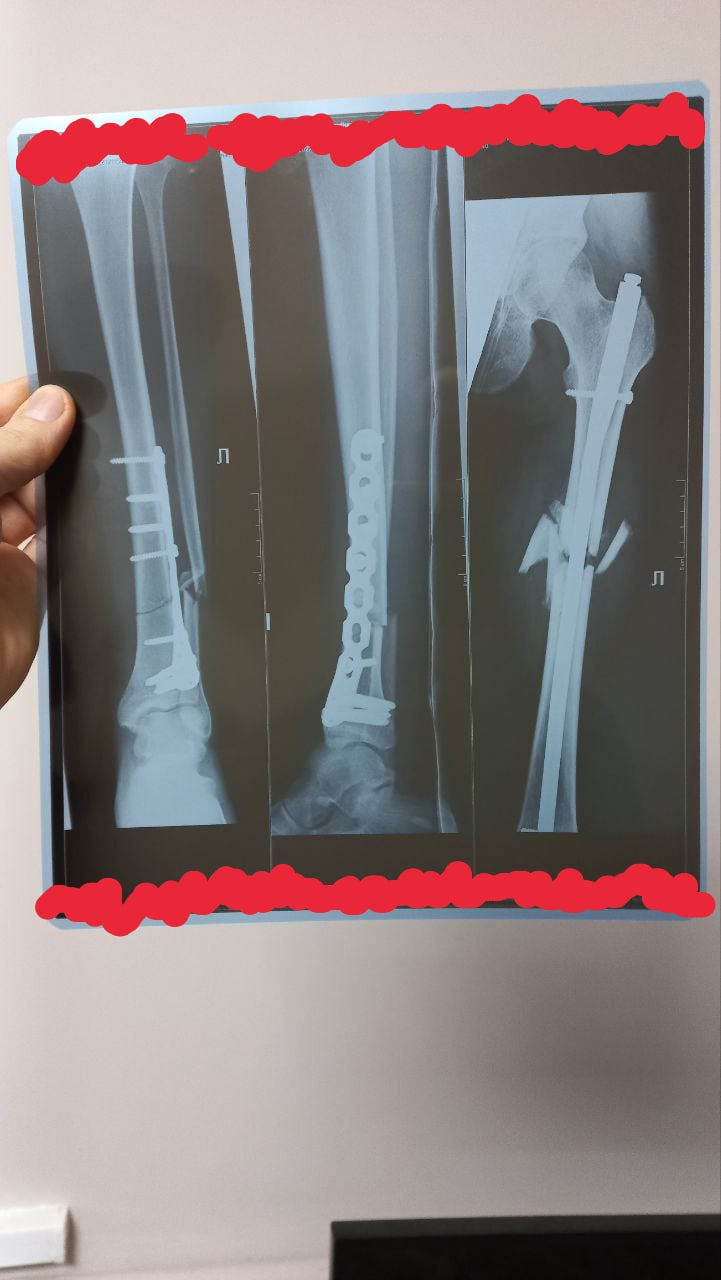

ТРАВМ-тред. Анончик, в последние дни сезона меня торпедировала коробка. Переломал все кости левой н /dcp/